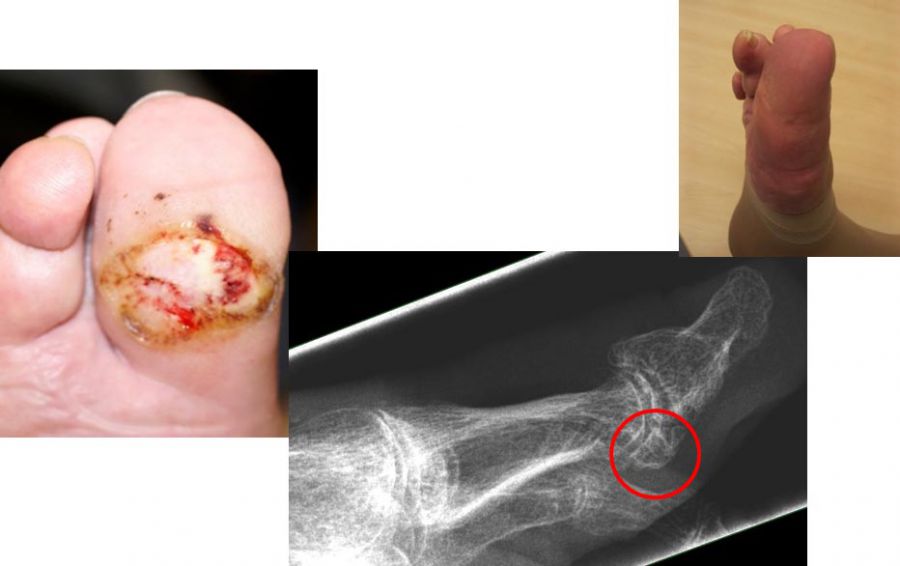

Chronische Ulcera führen längerfristig zu einer oberflächlichen Infektion des Fußes. Über die Zeit kann sich die Infektion in tiefere Gewebsschichten ausbreiten und den Knochen befallen. Bei einem ungünstigen Verlauf kann der Fuß so stark geschädigt werden, dass eine Amputation nicht mehr zu vermeiden ist. Neben einer schlechten Durchblutung und einer verminderten Gefühlswahrnehmung des Fußes (Polyneuropathie) führen häufig mechanische Druckstellen durch Knochenkanten zu Hautschäden. Um frühzeitig die Entstehung von Hautläsionen zu vermeiden, können wird häufig empfohlen störende Knochenkanten durch kleine operative Eingriffe abzutragen, bevor es zu einer Druckstelle kommt.

- Operative Behandlung von Druckstellen durch Hallux valgus

Aufgrund einer Fehlstellung der Großzehe nach außen (Hallux valgus) kann es zu Druckstellen bzw. Hautläsionen zwischen der 1. und 2. Zehe sowie kommen. Gefährdet ist auch die Haut auf der Innenseite des Fußes über dem Großzehengrundgelenk. Sollten hier konservative Therapiemaßnahmen (Polsterung/Schuhzurichtung) versagen, ist eine operative Korrektur des Hallux valgus anzuraten. - Operative Behandlung von Druckstellen durch Hammerzehen

Bei Hallerzehenfehlstellung kann es zu Druckstellen bzw. Hautschäden an der Zehenspitze oder über dem Zehenmittelgelenk kommen.Sollten hier konservative Therapiemaßnahmen (Polsterung/Schuhzurichtung) versagen, ist eine operative Korrektur der Hammerzehe sinnvoll, bevor offene Stellen entstehen, die dann zu Eintrittspforten für Keime werden.

- Operative Behandlung von Druckstellen durch Knochenvorsprünge (Exostose)

Im Bereich des Fußes können an verschiedenen Stellen Knochenanbauten (Exostosen) z.B. im Rahmen von Arthrose zu Druckstellen und dann zu Hautschäden führen. Hier ist die prophylaktische Abtragung des Knochenüberstandes sinnvoll. Immer wieder verhindern auch Knochenkanten die Heilung einer schon vorhandenen Hautwunde. In vielen Fällen lassen sich heute solche Knochenkannten minimalinvasiv in der sog. „Schlüssellochtechnik“ ohne große Operation entfernen.

Zum Lesen der Bildbeschreibung und Vollansicht bitte Bild anklicken. Fotos: Alexander Mehlhorn

- Operative Behandlung von Druckstellen durch Überlänge eines oder mehrerer Mittelfußknochen

Anlagebedingt oder nach Amputationen kann es zu einer Überlänge von einem Mittelfußknochen relativ zu den anderen Mittelfußknochen kommen. Dies führt zu einer erhöhten Druckbelastung an der Fußsohle. Zunächst treten Schwielen auf, im Verlauf kommt es dann zu offenen Stellen und einem Ulkus. Sollten hier konservative Therapiemaßnahmen (Polsterung/Schuhzurichtung) versagen, ist eine operative Verkürzung oder Anhebung des entsprechenden Mittelfußknochens sinnvoll, um den Druck zu reduzieren. Auch dies ist heute meist minimalinvasiv in Schlüssellochtechnik möglich.